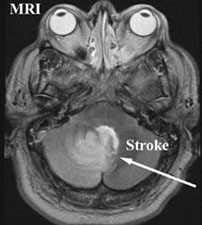

MRI or angiography are adjunct diagnostic methods. Magnetic resonance imaging can be used to create pictures of the brain and can also be used to create pictures of a blood vessel so called MR angiogram (MRA).

By these techniques the doctors can pinpoint the area of stroke in the brain as well as the area of blockage of the vessels.

T2 MR